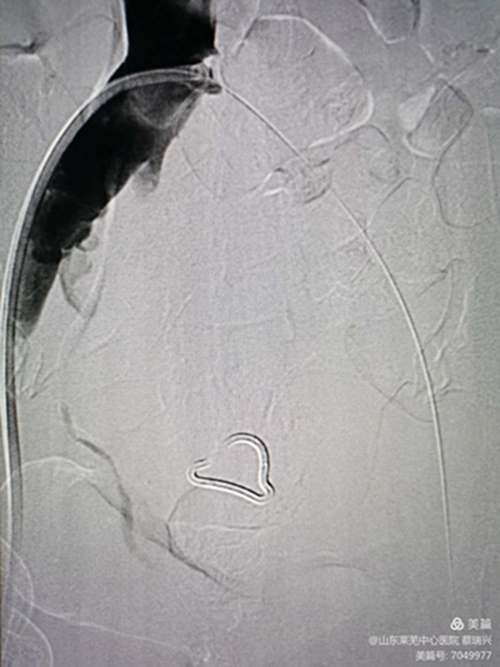

后擴(kuò)滿意后

再造影見狹窄消失,血流順暢。